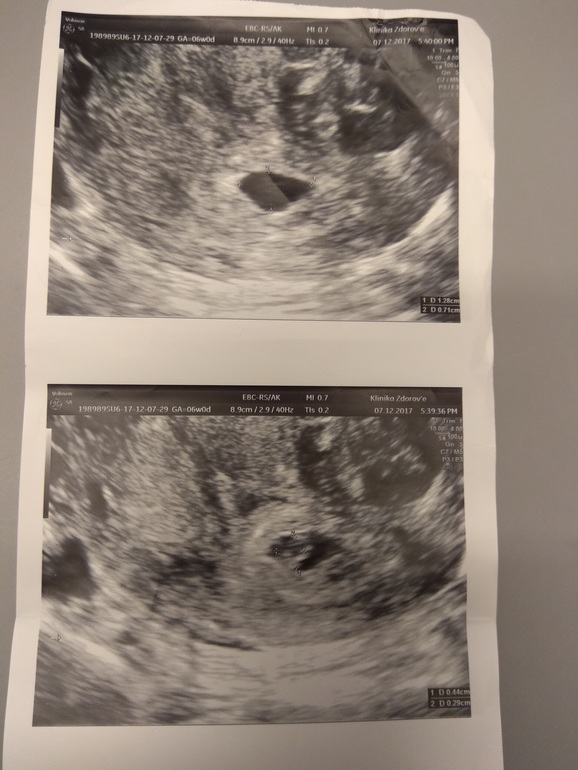

первая картинка-последнее узи последняя картинка-первое узи средняя картинка-оба УЗИ: первое УЗИ (вверху) и второе УЗИ (внизу)

Поняла) Лен,у тебя ПЯ на узи от 12.12 прям хорошее, ттт. И эмбриончику там прям свободно. Замер яйца не совсем мне кажется корректный был. Или действительно, свд замерили - средний внутренний диаметр. А если отрезком мерять - то по длине ПЯ точно мм 20, а то и более даже. Я боялась, вдруг эмбрион быстрее яйца растет и как бы тесно там, но даже по фото этого нет. Расслабляйся и выдыхай давай! По узи хорошо у тебя, и по размерам догоните!